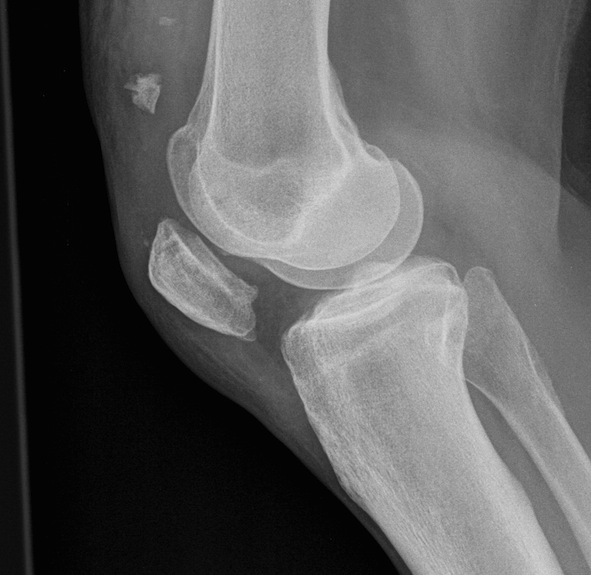

Patella Baja

Diagnosis

Blackburne-Peel ratio at 30 degrees flexion